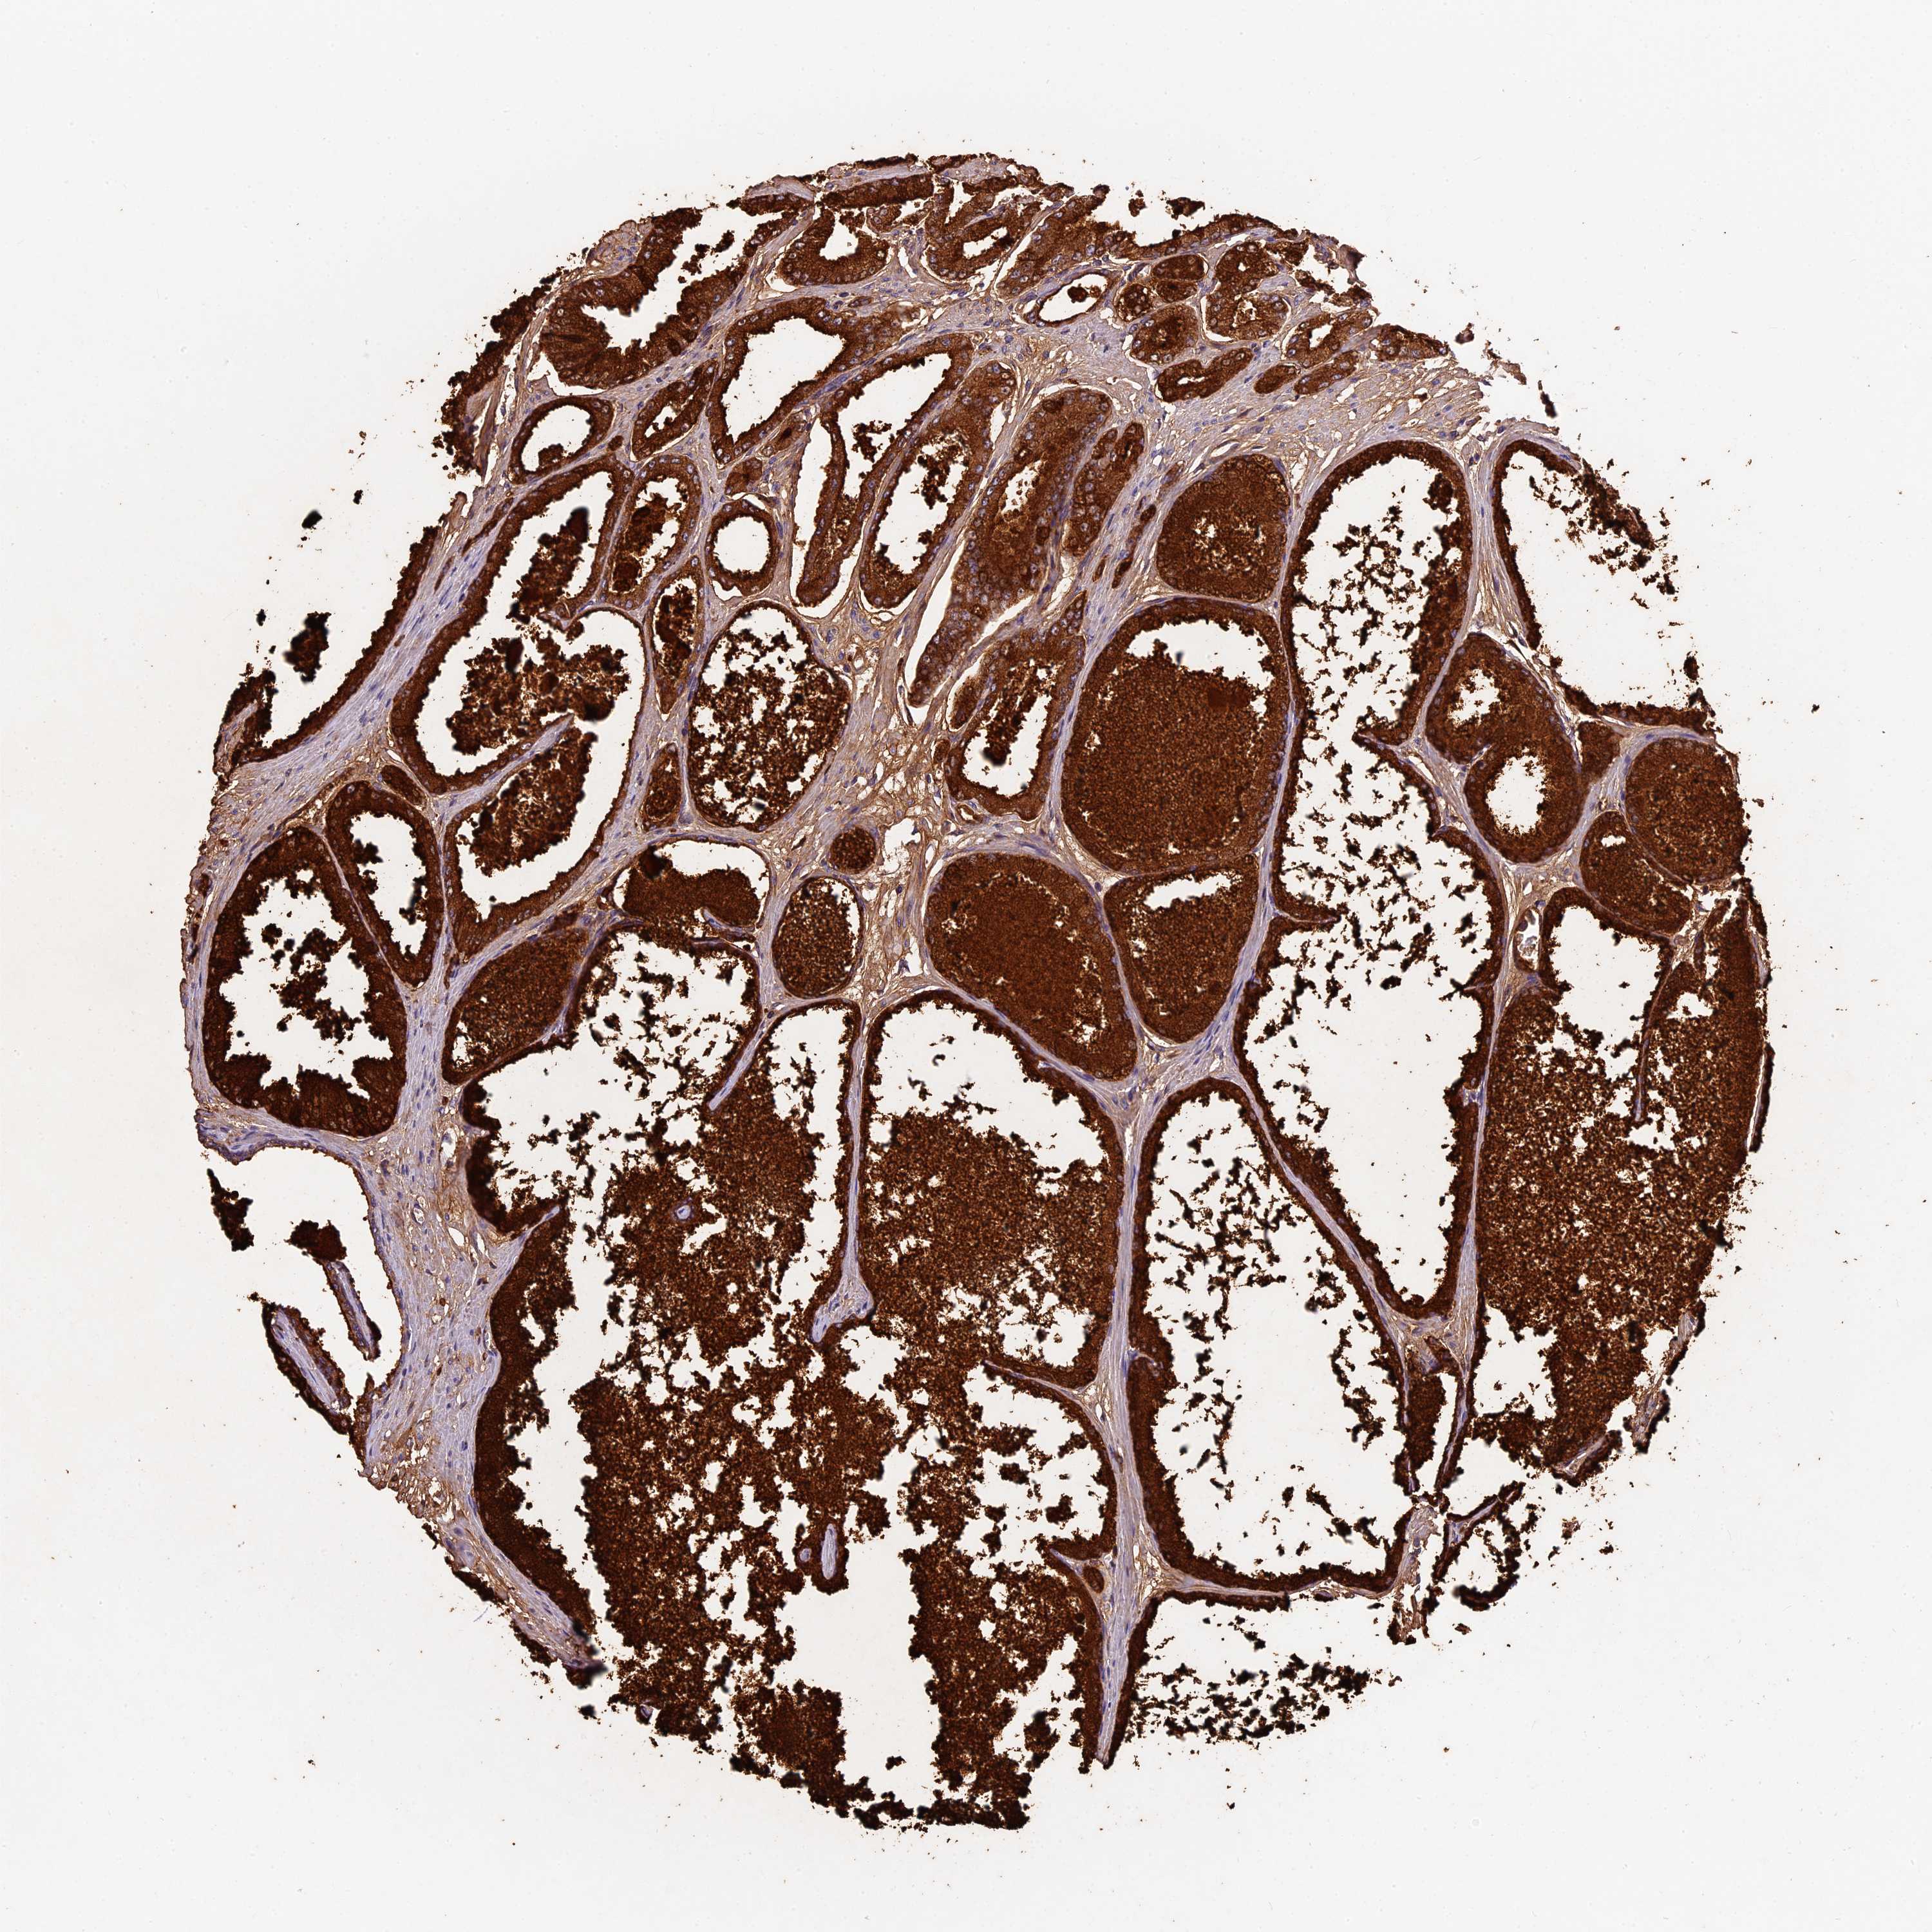

PROSTATE CANCER - Protein expressioni

A mouse-over function shows sample information and annotation data. Click on an image to view it in a full screen mode. Samples can be filtered based on level of antibody staining by selecting one or several of the following categories: high, medium, low and not detected. The assay and annotation is described here.

Antibody stainingi

Antibody staining in the annotated cell types in the current human tissue is reported as not detected, low, medium, or high, based on conventional immunohistochemistry profiling in selected tissues. This score is based on the combination of the staining intensity and fraction of stained cells.

Each image is clickable and will lead to virtual microscopy that enables deeper exploration of all samples and also displays staining intensity scores, fraction scores and subcellular localization as well as patient and tissue information for each sample.

Antibody HPA039533

Antibody HPA040355

Staining

High

Medium

Low

Not detected

Intensity

Strong

Moderate

Weak

Negative

Quantity

>75%

75%-25%

<25%

None

Location

Nuclear

Cytoplasmic/membranous

Cytoplasmic/membranous,nuclear

Adenocarcinoma, High grade

Adenocarcinoma, Low grade